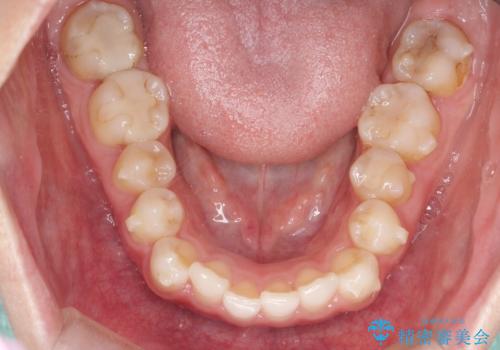

- 上下の前歯のがたつきを主訴に来院されました。

目立たない装置がご希望で、インザラインによるマウスピース矯正にて治療を行うこととなりました。